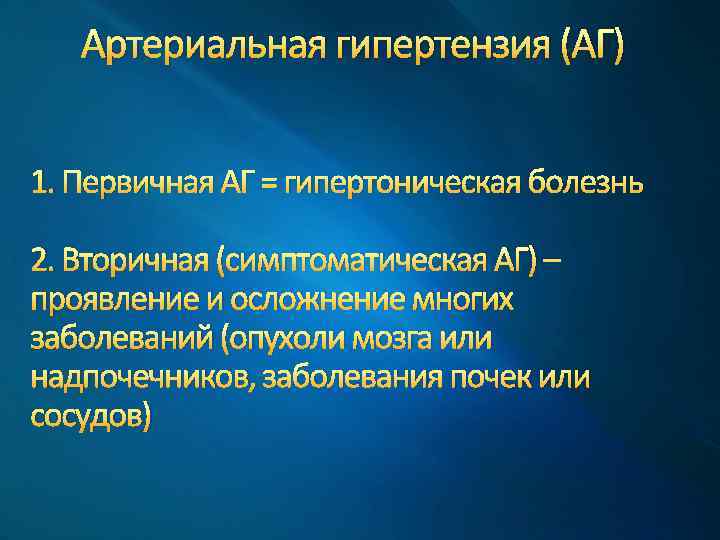

Артериальная гипертензия (АГ) 1. Первичная АГ = гипертоническая болезнь 2. Вторичная (симптоматическая АГ) – проявление и осложнение многих заболеваний (опухоли мозга или надпочечников, заболевания почек или сосудов)